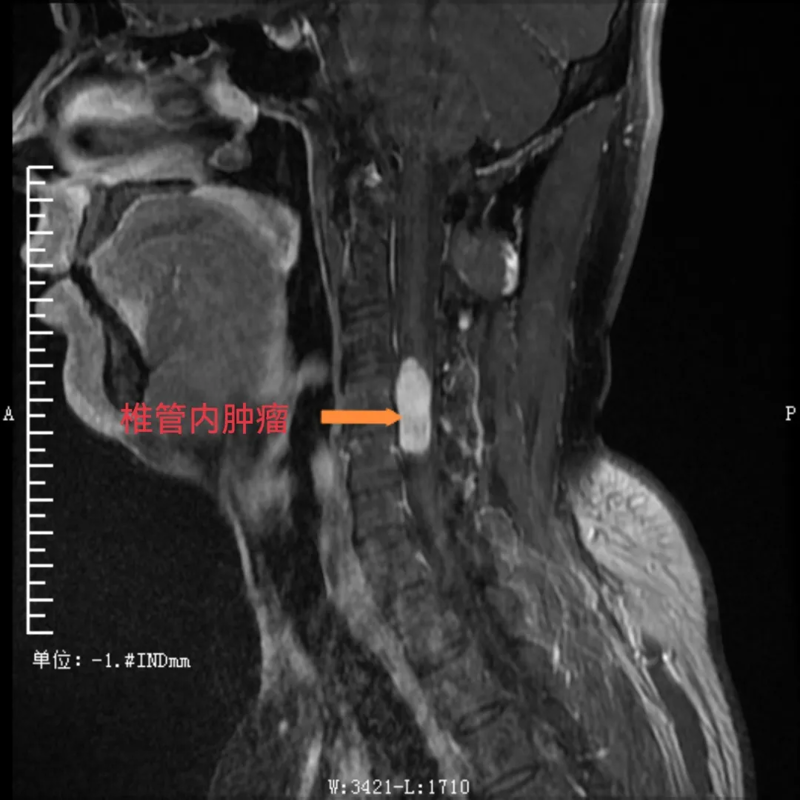

患者潘某(化名),是一位38岁的男性,一直被“左上肢感觉异常、乏力”的症状困扰8个多月。起初,他在贵州荔波县当地医院进行诊治,后根据患者意愿,转到河池市三医院神经外科接受进一步诊疗,到院后,经检查,明确了他的病因:原来是颈椎4-5节段椎管内长了肿瘤。这一肿瘤的存在严重影响了他的神经功能,导致了上肢的不适症状。对于患者来说,这无疑是一个沉重的打击。

术前,可见椎管内肿瘤

面对潘某的病情,河池市三医院的医务人员深知责任重大,立即安抚患者并提供心理疗法,积极为他制定治疗方案。医务部组织神经外科、脊柱外科、麻醉科、重症医学科等院内多学科MDT讨论,仔细研究患者的各项检查结果,不放过任何一个细节。考虑到颈椎部位的手术风险极高,稍有不慎就可能对患者的神经造成不可挽回的损伤。